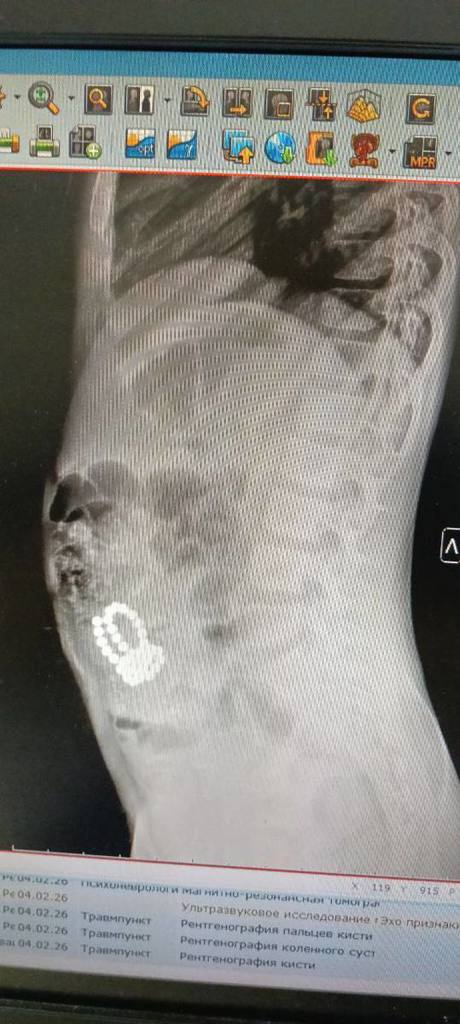

«По линии скорой медицинской помощи в приемное отделение доставили восьмилетнего мальчика с жалобами на боли в области живота и многократную рвоту. После проведения всех диагностических мероприятий, врачи обнаружили множетсво инородных тел в организме. Пациенту экстренно проведена операция — диагностическая лапароскопия, лапаротомия, ушивание перфораций тонкой кишки, удалено 44 магнитных шарика», - рассказывает заведующий детским хирургическим отделением Республиканской детской клинической больницы Минздрава Чувашии Михаил Порфирьев.

Через некоторое время родители доставили в больницу четырехлетнего брата мальчика для проведения обследования подозревая, что младший ребенок тоже мог проглотить магнитные шарики. К сожалению, их опасения подтвердились. В брюшной полости обнаружили 10 магнитиков. Юному пациенту также была проведена экстренная операция — лапаротомия, ушивания перфораций тонкой кишки, удаление магнитов. В данном случае братья вовремя получили необходимую медицинскую помощь.